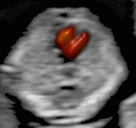

Zudem werden die Entwicklung des Kindes und seine Organe untersucht. Dabei wird  großen Wert auf das kindliche Herz gelegt, denn viele Herzfehler können bereits zu diesem frühen Zeitpunkt erkannt werden, obwohl das Herz zu diesem Zeitpunkt erst so groß ist wie ein Reiskorn.

In der Regel wird für diese Untersuchung eine Überweisung vom betreuenden Frauenarzt ausgestellt, z. B. wenn im Rahmen der üblichen in den Mutterschaftsrichtlinien empfohlenen Ultraschalluntersuchung eine Auffälligkeit gesehen wurde. Weitere Gründe für eine Überweisung sind Risikoschwangerschaften oder auch der Wunsch der Eltern nach einer zusätzlichen Absicherung. Neben der allgemeinen Entwicklung des Kindes können hier –noch genauer als im Ersttrimesterscreening – alle Organe des ungeborenen Kindes begutachtet werden. Zusätzlich wird mittels Dopplersonographie die kindliche Versorgung und die des Mutterkuchens überprüft. Da Herzfehlbildungen zu den häufigsten angeborenen Fehlbildungen gehören, stellt die detaillierte fetale Echokardiographie (Untersuchung des kindlichen Herzens) einen wichtigen Bestandteil der Untersuchung dar. Dabei werden sowohl die Anatomie des Herzens als auch die Blutflüsse begutachtet.

Echokardiografie